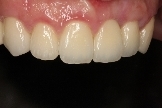

病患治療後,最終假牙完成照。

病患恢復自信的笑容。